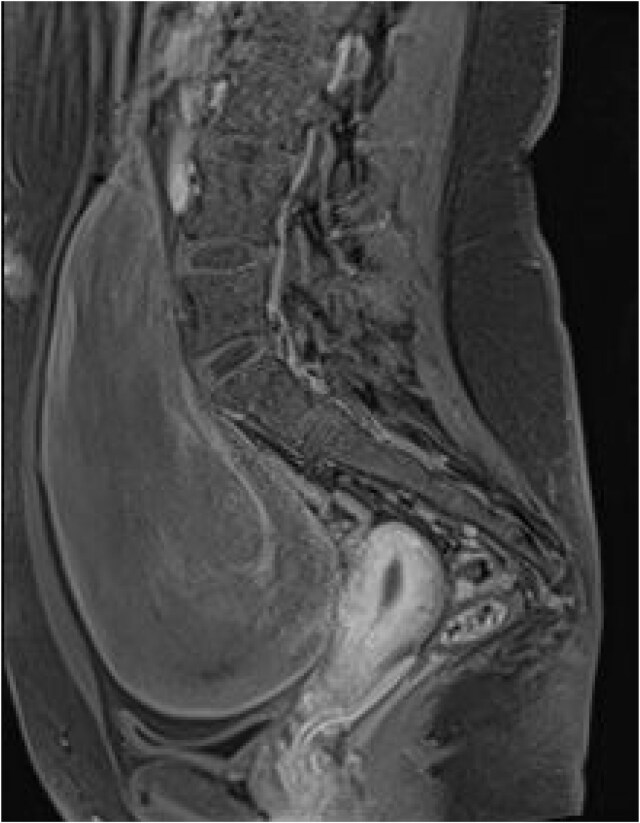

Large extraluminal gastrointestinal stromal tumours (GISTs) are rare, with varied presentations and patient profiles. This report discusses the case of a 22-year-old female presenting with a 4-month history of lower abdominal pain, weight loss, and recurrent urinary tract infections. Imaging revealed a large intra-abdominal mass (9.3 × 15.3 × 18.9 cm) originating from the stomach, extending into the pelvis, and compressing adjacent structures. During surgery, the mass was found to arise from the lesser curvature of the stomach and adhered to the transverse colon, with non-adherent extension into the pelvis and compression of adjacent organs. A gastric wedge resection and transverse colectomy were performed with aim of achieving a R0 resection. Histopathological analysis confirmed a GIST and positive resection margins. A plan for adjuvant imatinib was initiated in accordance with the European Society for Medical Oncology (ESMO) guidelines. This article details the challenges faced in the management of such a rare presentation and highlights similar reports.